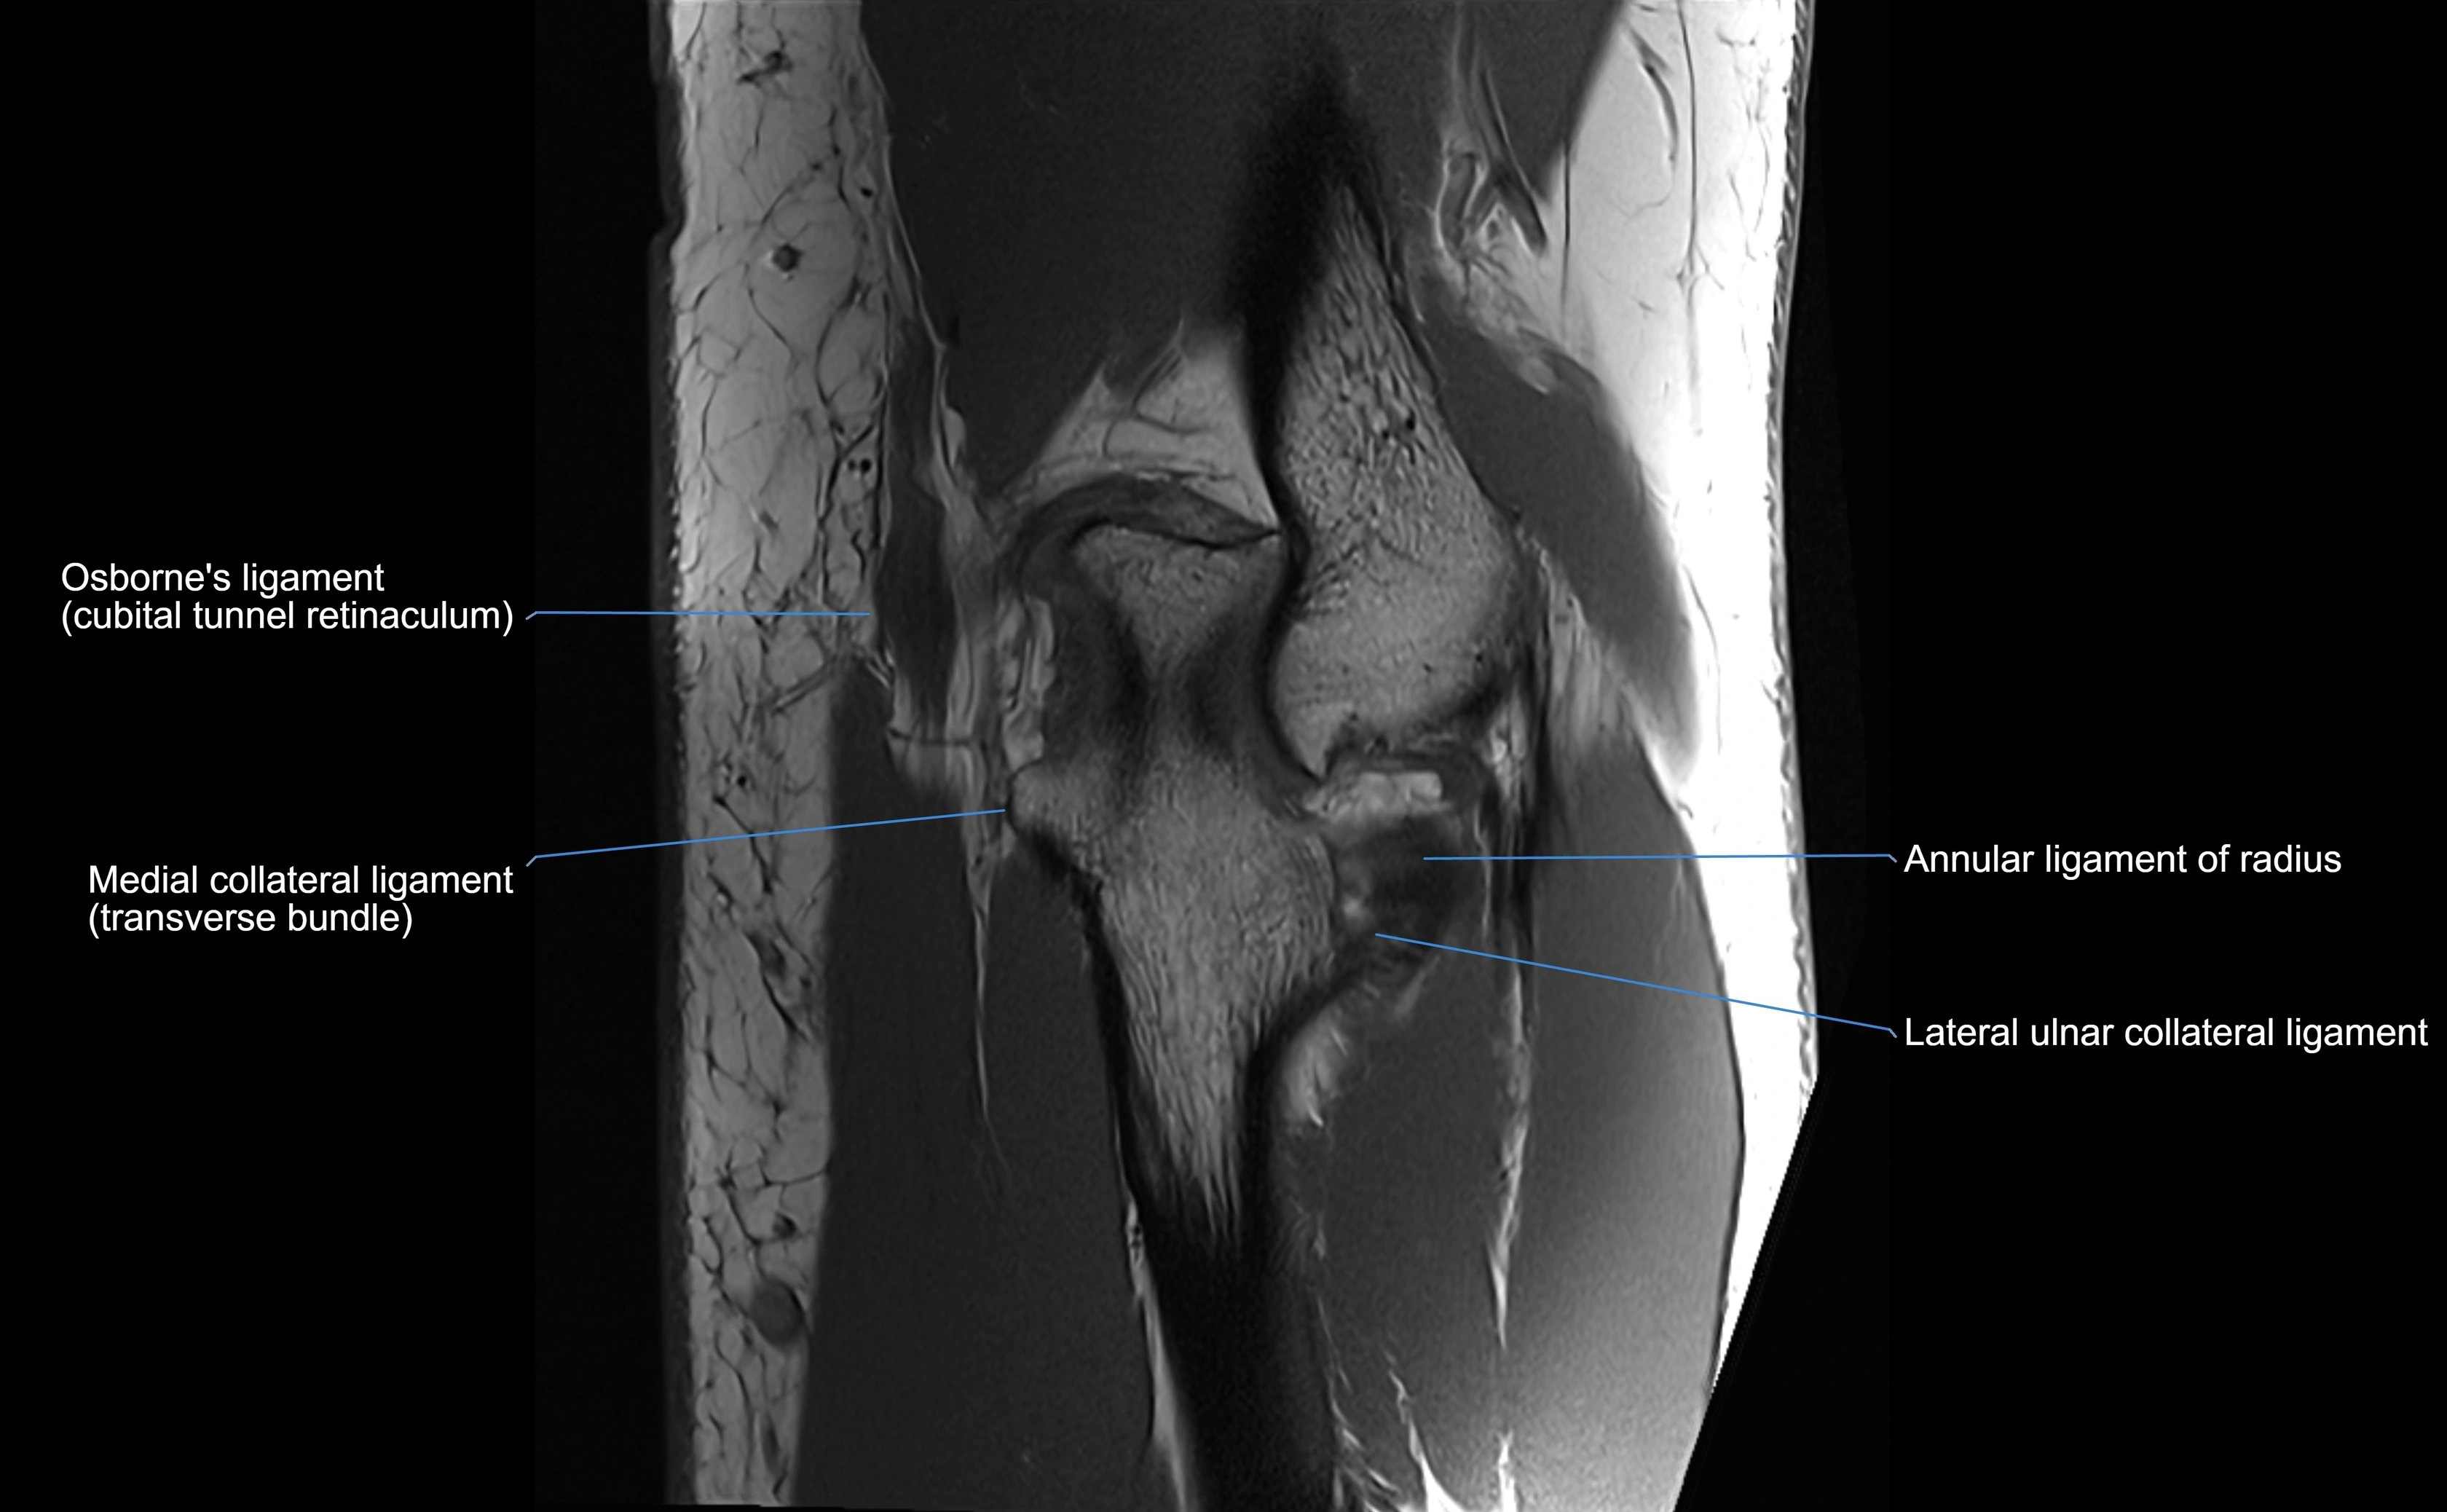

MRI Appearance

T1-weighted images:

• Ligament: low signal intensity (dark), appearing as a continuous band around the radial head.

• Adjacent fat and marrow: bright, creating contrast with the ligament.

• Thickening or disruption indicates injury or fibrosis.

• Joint capsule and synovium seen as thin low-signal lines contiguous with ligament margins.

T2-weighted images:

• Ligament: low signal (dark) with clear delineation from joint fluid.

• Fluid or edema: bright hyperintense, separating or surrounding the ligament in partial tears.

• Complete tear: discontinuity or non-visualization of ligament fibers, often with joint effusion.

MRI images

image